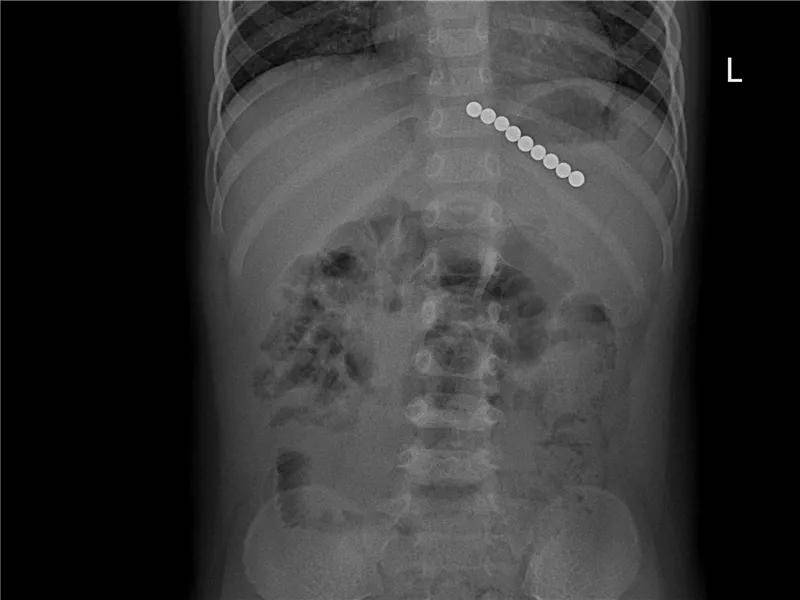

6岁·磁力珠

5小时前不慎误服磁力珠,未见呕吐,无腹痛。